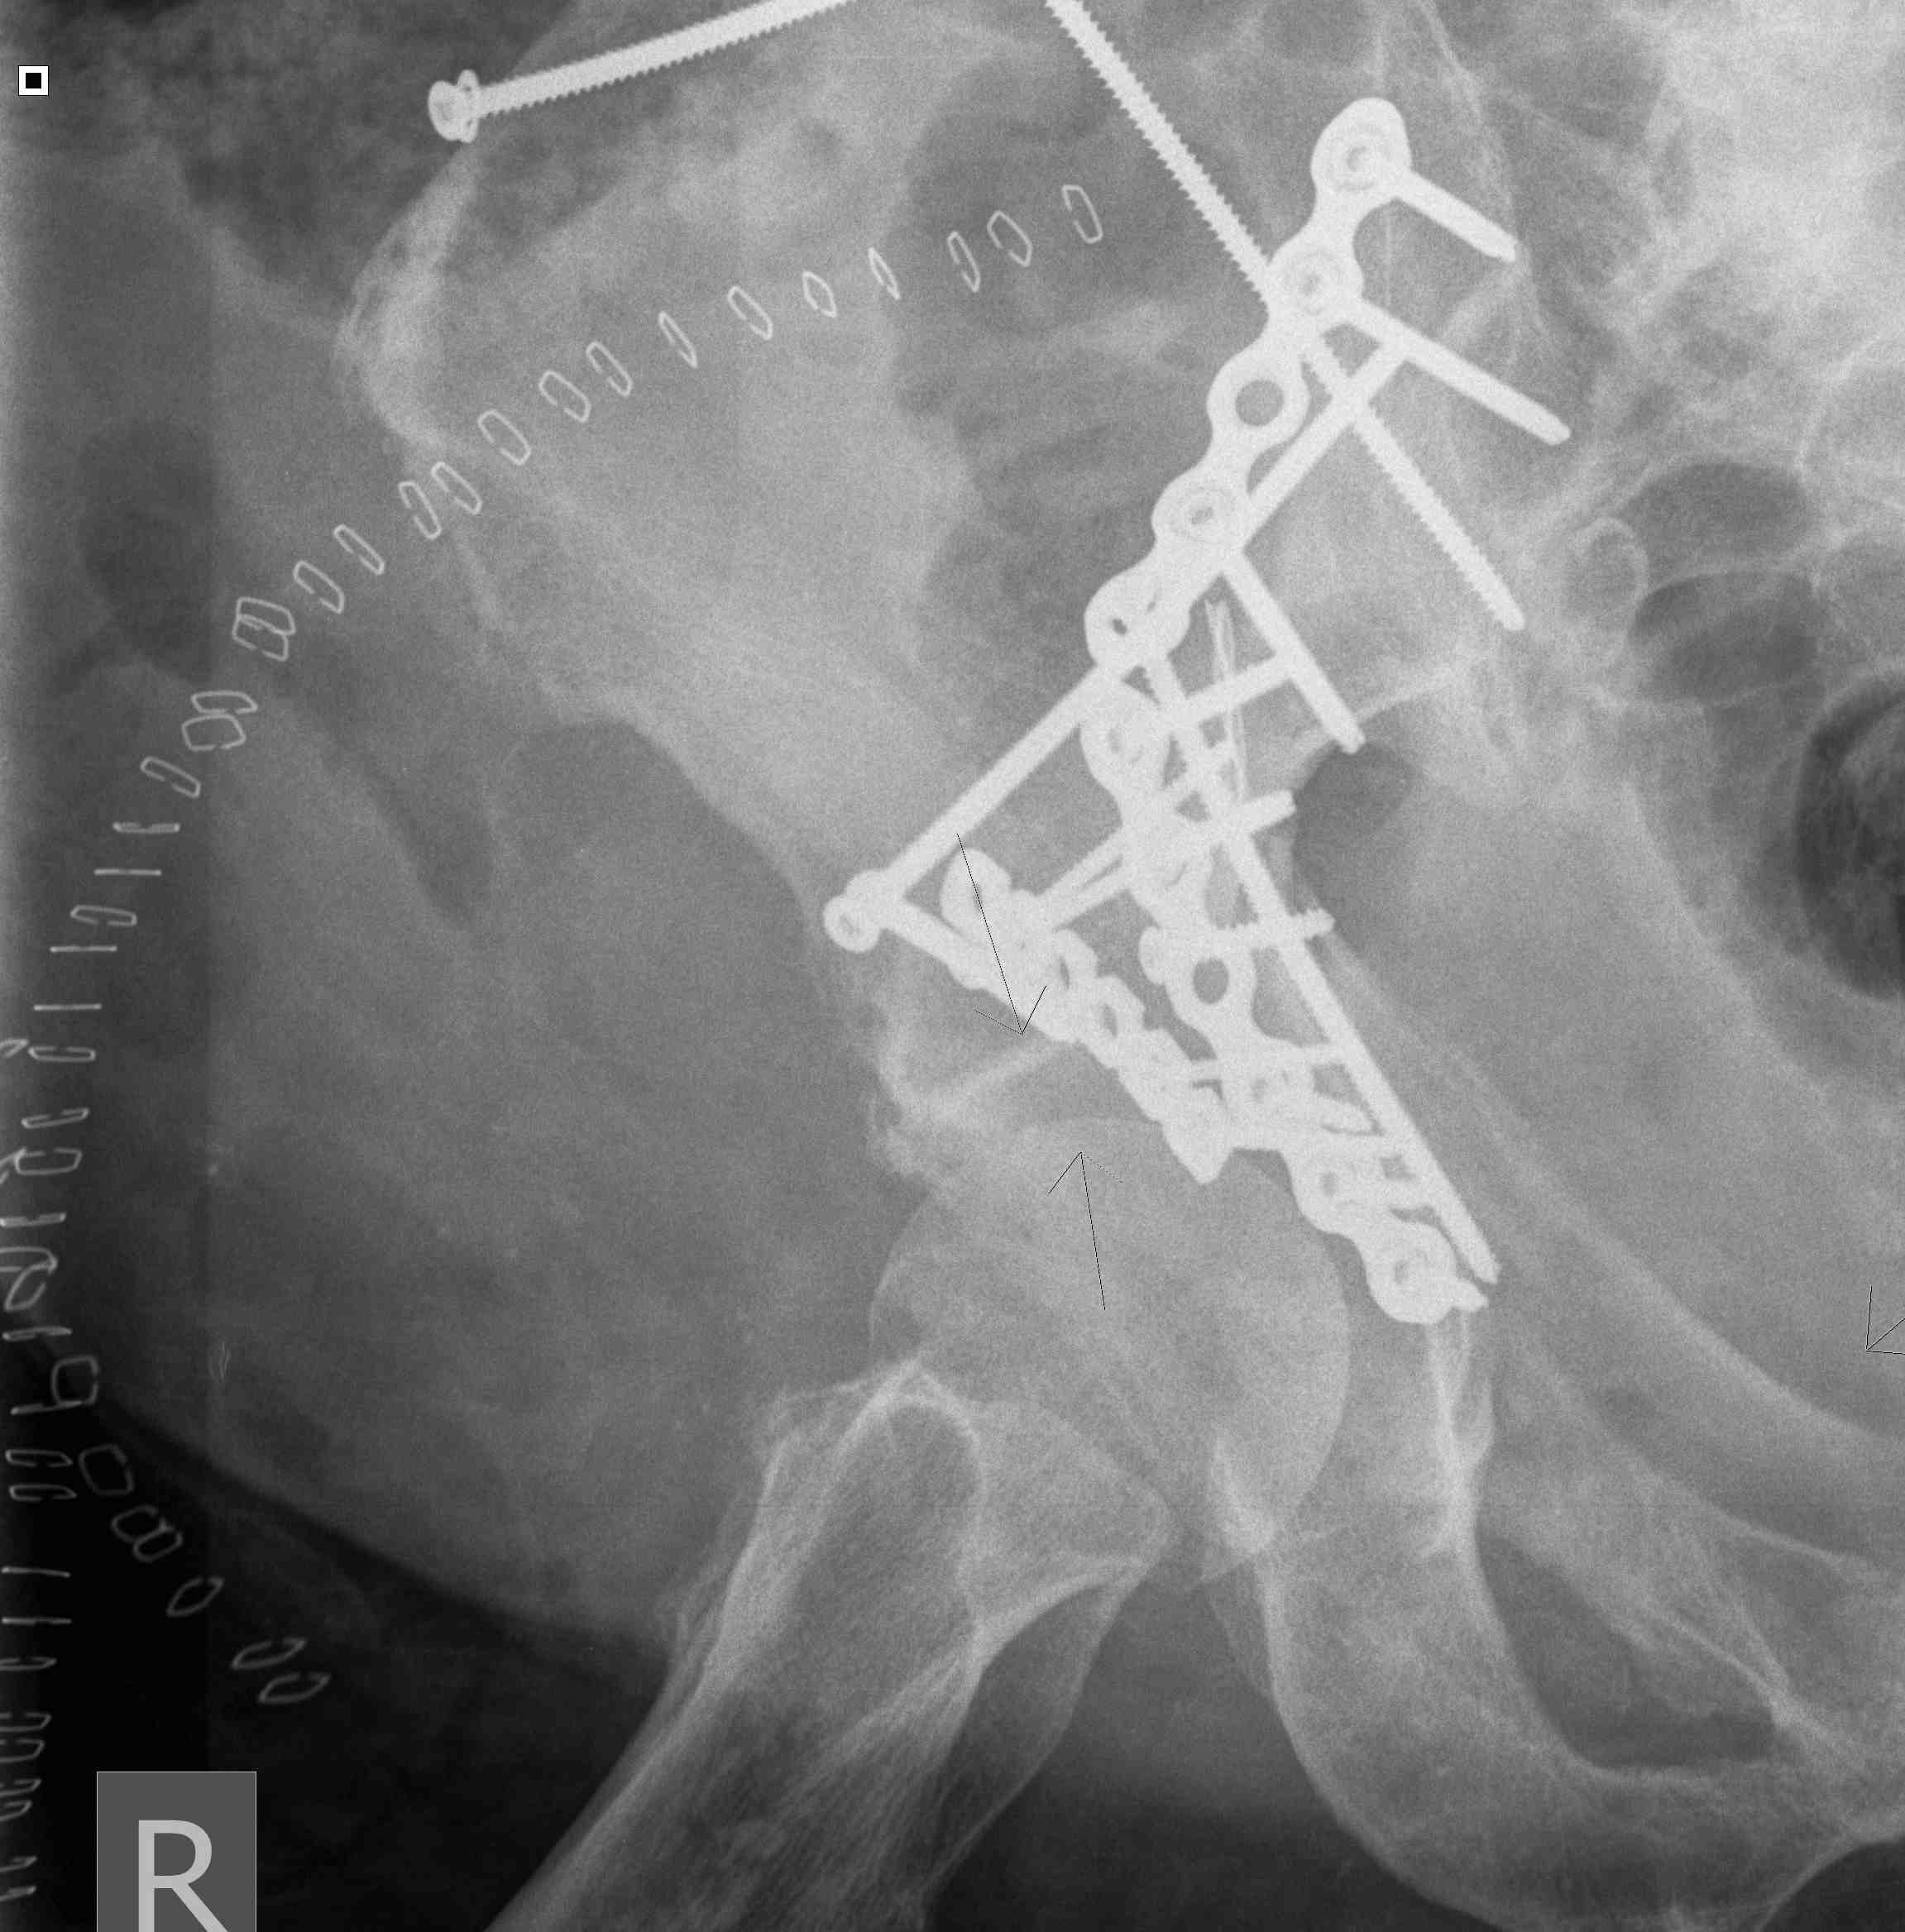

Posterior Column & Wall Fracture

Reduction

- buttress plate from Ischial Tuberosity to Ilium

- contour or use pre-contoured

- screws at plate extremities

- often 2 parallel plates if wall and column fracture

II to ensure screws not in acetabulum